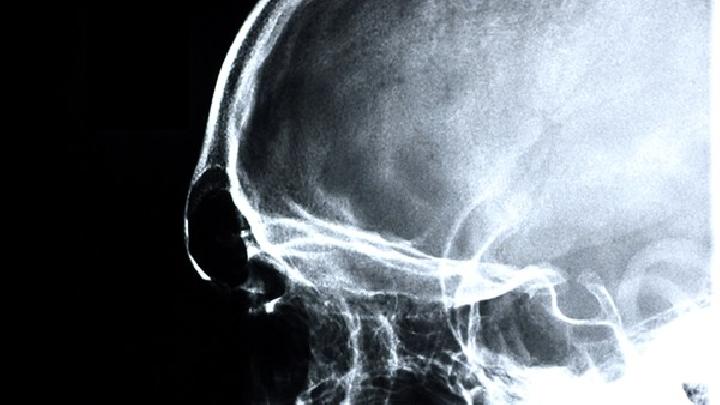

通常是指在出生前到出生后一个月内由各种原因引起的非进行性脑损伤或脑发育异常所导致的中枢性运动障碍。小儿脑瘫的症状可以从以下几个方面识别: